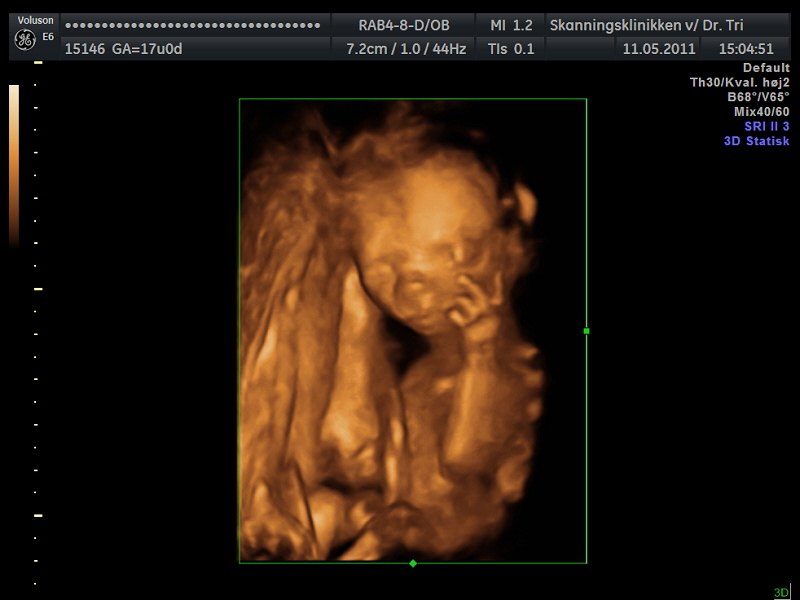

Mange tak hehe han blottede sine ædlere dele helt vildt efterfulgt at et stort smil og så kastede han lige håndtegn til mor og far

scanningsdamen var helt solgt hehe og selfølgelig osse mor og far